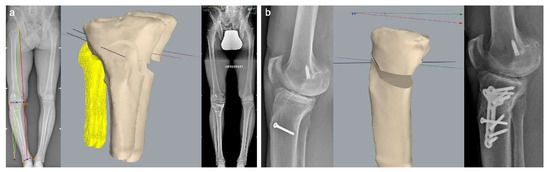

4.2. Customized System for Valgus HTO

4.4. Imaging Evaluation